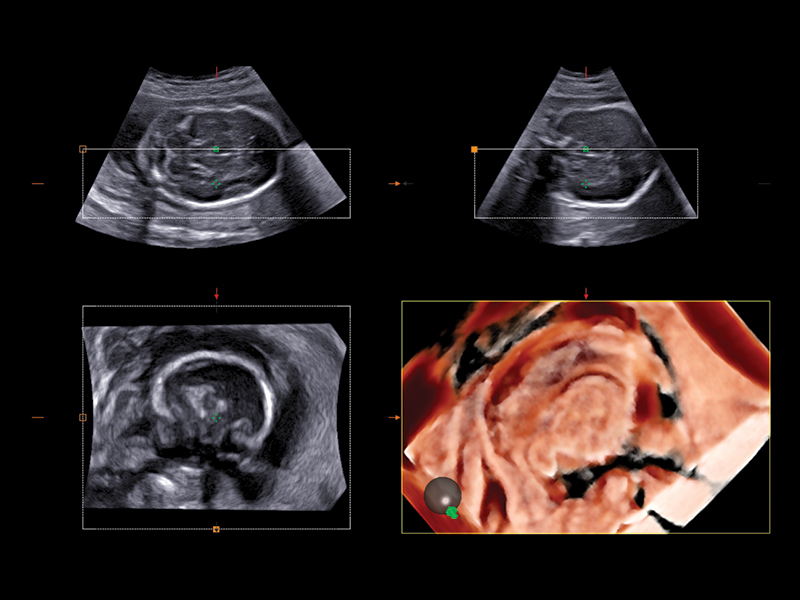

Realistic 3D/4D Depiction of the Fetus

Esaote attaches great value to the quality of its 3D/4D imaging in order to provide very detailed picture of the baby’s features, depending on the stage of fetal development. Its environment is provided by different modalities, based on how the volume can be processed and rendered.

Esaote XLight technology, with its realistic diffusion effects and shadows, emphasizes the anatomical details of the fetus in baby face scanning; XGlass creates a transparency effect; bone rendering is ideal to study the baby’s spine; TSI (Thick Slice Imaging) is suitable for well-defined and confined structures, such as the corpus callosum; finally, XSTIC accurately evaluates the fetal heart.